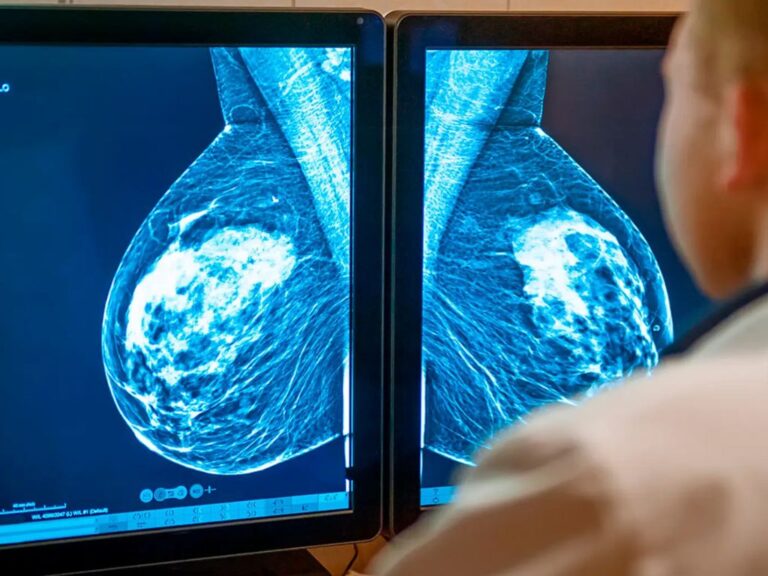

Cáncer de mama triple negativo: dianas terapéuticas y decisión clínica

El cáncer de mama triple negativo (TNBC) representa ~10–15% de los tumores mamarios y se caracteriza por ausencia de RE/RP y de amplificación de HER2. Es biológicamente heterogéneo y con mayor agresividad clínica. El abordaje actual integra histopatología, inmunohistoquímica y un perfil molecular dirigido a biomarcadores con impacto pronóstico y/o terapéutico (p. ej., BRCA1/2 para inhibidores PARP, PD-L1 para inmunoterapia, NTRK para terapias agnósticas, MSI-H para indicación inmunoterapéutica, EGFR/VEGF por IHQ).

El TNBC supone ~10–15% de los cánceres de mama y suele asociarse a mayor tasa de proliferación y a presentación en mujeres más jóvenes que otros subtipos. Su heterogeneidad biológica y la asociación frecuente con fenotipo basal-like, así como su pronóstico clínico adverso es mayor en comparación con otros subtipos.